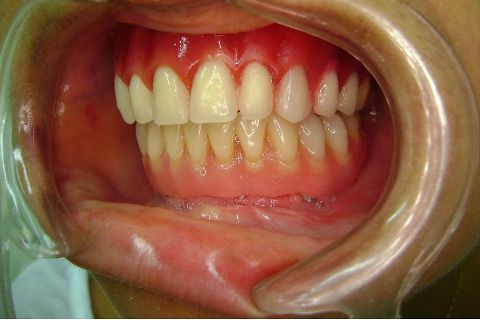

Atualização do caso clínico que já postei, "REABILITAÇÃO EM MAXILA ATRÓFICA COM IMPLANTES", um caso que inclui expansão do rebordo estreito com cinzel e martelo, expansores rosqueáveis, enxerto e instalação dos implantes distais inclinados tangenciando seio maxilar. Inclui esvaziamento do forame nasopalatino e preenchimento com biomaterial para instalação de dois implantes próximos dele. Cirurgia realizada em única sessão, com instalação dos 6 implantes. Para os colegas que não conheceram e/ou esqueceram da apresentação, este é o resumo do caso na fase cirúrgica.http://www.youtube.com/watch?v=BtvexFexRPA&hd=1

FASE PROTÉTICA DA REABILITAÇÃO EM MAXILA ATRÓFICA...incluindo a reabertura, instalação dos minipilares e PTR provisória reembasada sobre os cilindros de proteção.